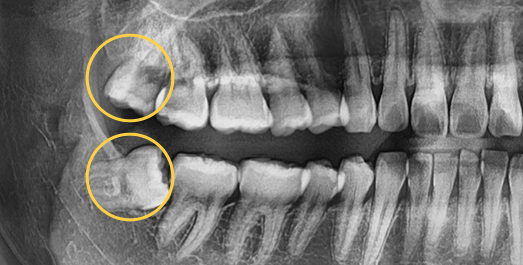

• Horizontally

impacted wisdom tooth

• Angulated

• Vertically